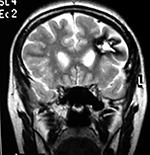

EJEMPLO DE CASO CLÍNICO (8)

Paciente femenino de 29 años de edad con historial de cefalea crónica que presenta súbitamente disdiadococinesia y dismetría izquierda.

El estudio de RMN presenta una lesión bien circunscrita en hemisferio cerebeloso izquierdo con periferia de predominio hiperintenso en T1 y T2, y centro hipointenso, edema perilesional mínimo, así como una imagen de un vaso venoso alimentador que recorre hacia el ángulo pontocerebeloso izquierdo.

Se realizó una craniectomía suboccipital paramedial derecha, así como un abordaje transcortical en el hemisferio cerebeloso izquierdo llegando a la región perilesional de aspecto amarillento, posteriormente se observa una lesión oscuro-verdoso de contenido hemático antiguo, retirando la cápsula y su contenido en la totalidad.

La evolución clínica de la paciente fue satisfactoria solo preservando la dismetría como secuela.

El resultado histopatológico fue consistente en angioma cavernoso.

El estudio de control de RMN se observa la brecha quirúrgica y ausencia de lesión (figs. 1, 2 y 3).

Figura 1:

Lesión cerebelosa izquierda ponderaciones en T1 y T2, la flecha señala vaso nutricio hacia el ángulo pontocerebeloso izquierdo, se puede observar el centro de intensidad heterogénea con contenido quístico multiloculado y edema perilesional leve.